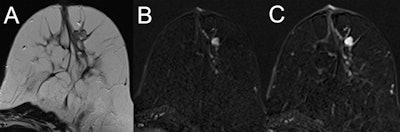

MRI of a 47-year-old high-risk patient (A, T2-weighted; B and C, subtracted early and late contrast-enhanced, T1-weighted images) shows a rather circumscribed mass lesion with heterogeneous internal enhancement and washout, corresponding to a Kaiser score of 8. Histology revealed a luminal-type invasive lobular cancer, B5b. Images courtesy of European Radiology. MRI of a 39-year-old high-risk patient (A, T2-weighted; B and C, subtracted early and late contrast-enhanced, T1-weighted images) shows a circumscribed mass lesion with heterogeneous internal enhancement and persistent signal increase, corresponding to a Kaiser score of 1. Note the fibroadenoma-like T2-weighted correlate (A). Histopathology revealed a fibroadenoma, B2.

MRI of a 39-year-old high-risk patient (A, T2-weighted; B and C, subtracted early and late contrast-enhanced, T1-weighted images) shows a circumscribed mass lesion with heterogeneous internal enhancement and persistent signal increase, corresponding to a Kaiser score of 1. Note the fibroadenoma-like T2-weighted correlate (A). Histopathology revealed a fibroadenoma, B2."I can warmly recommend the Kaiser score to everyone, as it forces the reader to assess all relevant diagnostic criteria before coming to a conclusion," Baltzer noted. "Gut-feeling decisions (that regularly happened to me) are avoided."